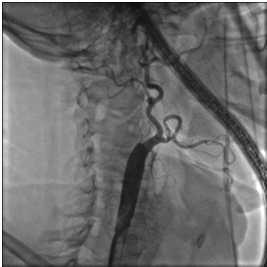

Выполнено контрольное дуплексное сканирование брахиоцефальных артерий, по результатам которого выявлен 80% стеноз устья правой внутренней сонной артерии (пВСА). Пиковая скорость кровотока в пВСА – 250 см/сек. Учитывая рецидивирующую клинику ТИА, гемодинамически-значимое поражение правой ВСА – больному рекомендована реваскуляризация в бассейне правой ВСА. Однако при селективной ангиографии брахиоцефальных артерий выявлена короткая окклюзия правой ВСА от устья.

Интракраниальные отделы кровоснабжаются из бассейна левой сонной артерии по Вилизиеву кругу.

Учитывая «симптомность» поражения сонной артерии, а также благоприятные анатомо-морфологические характеристики поражения и высокую вероятность успеха эноваскулярного лечения - принято решение о проведении ангиопластики со стентированием правой внутренней сонной артерии с использованием проксимальной системы защиты головного мозга.